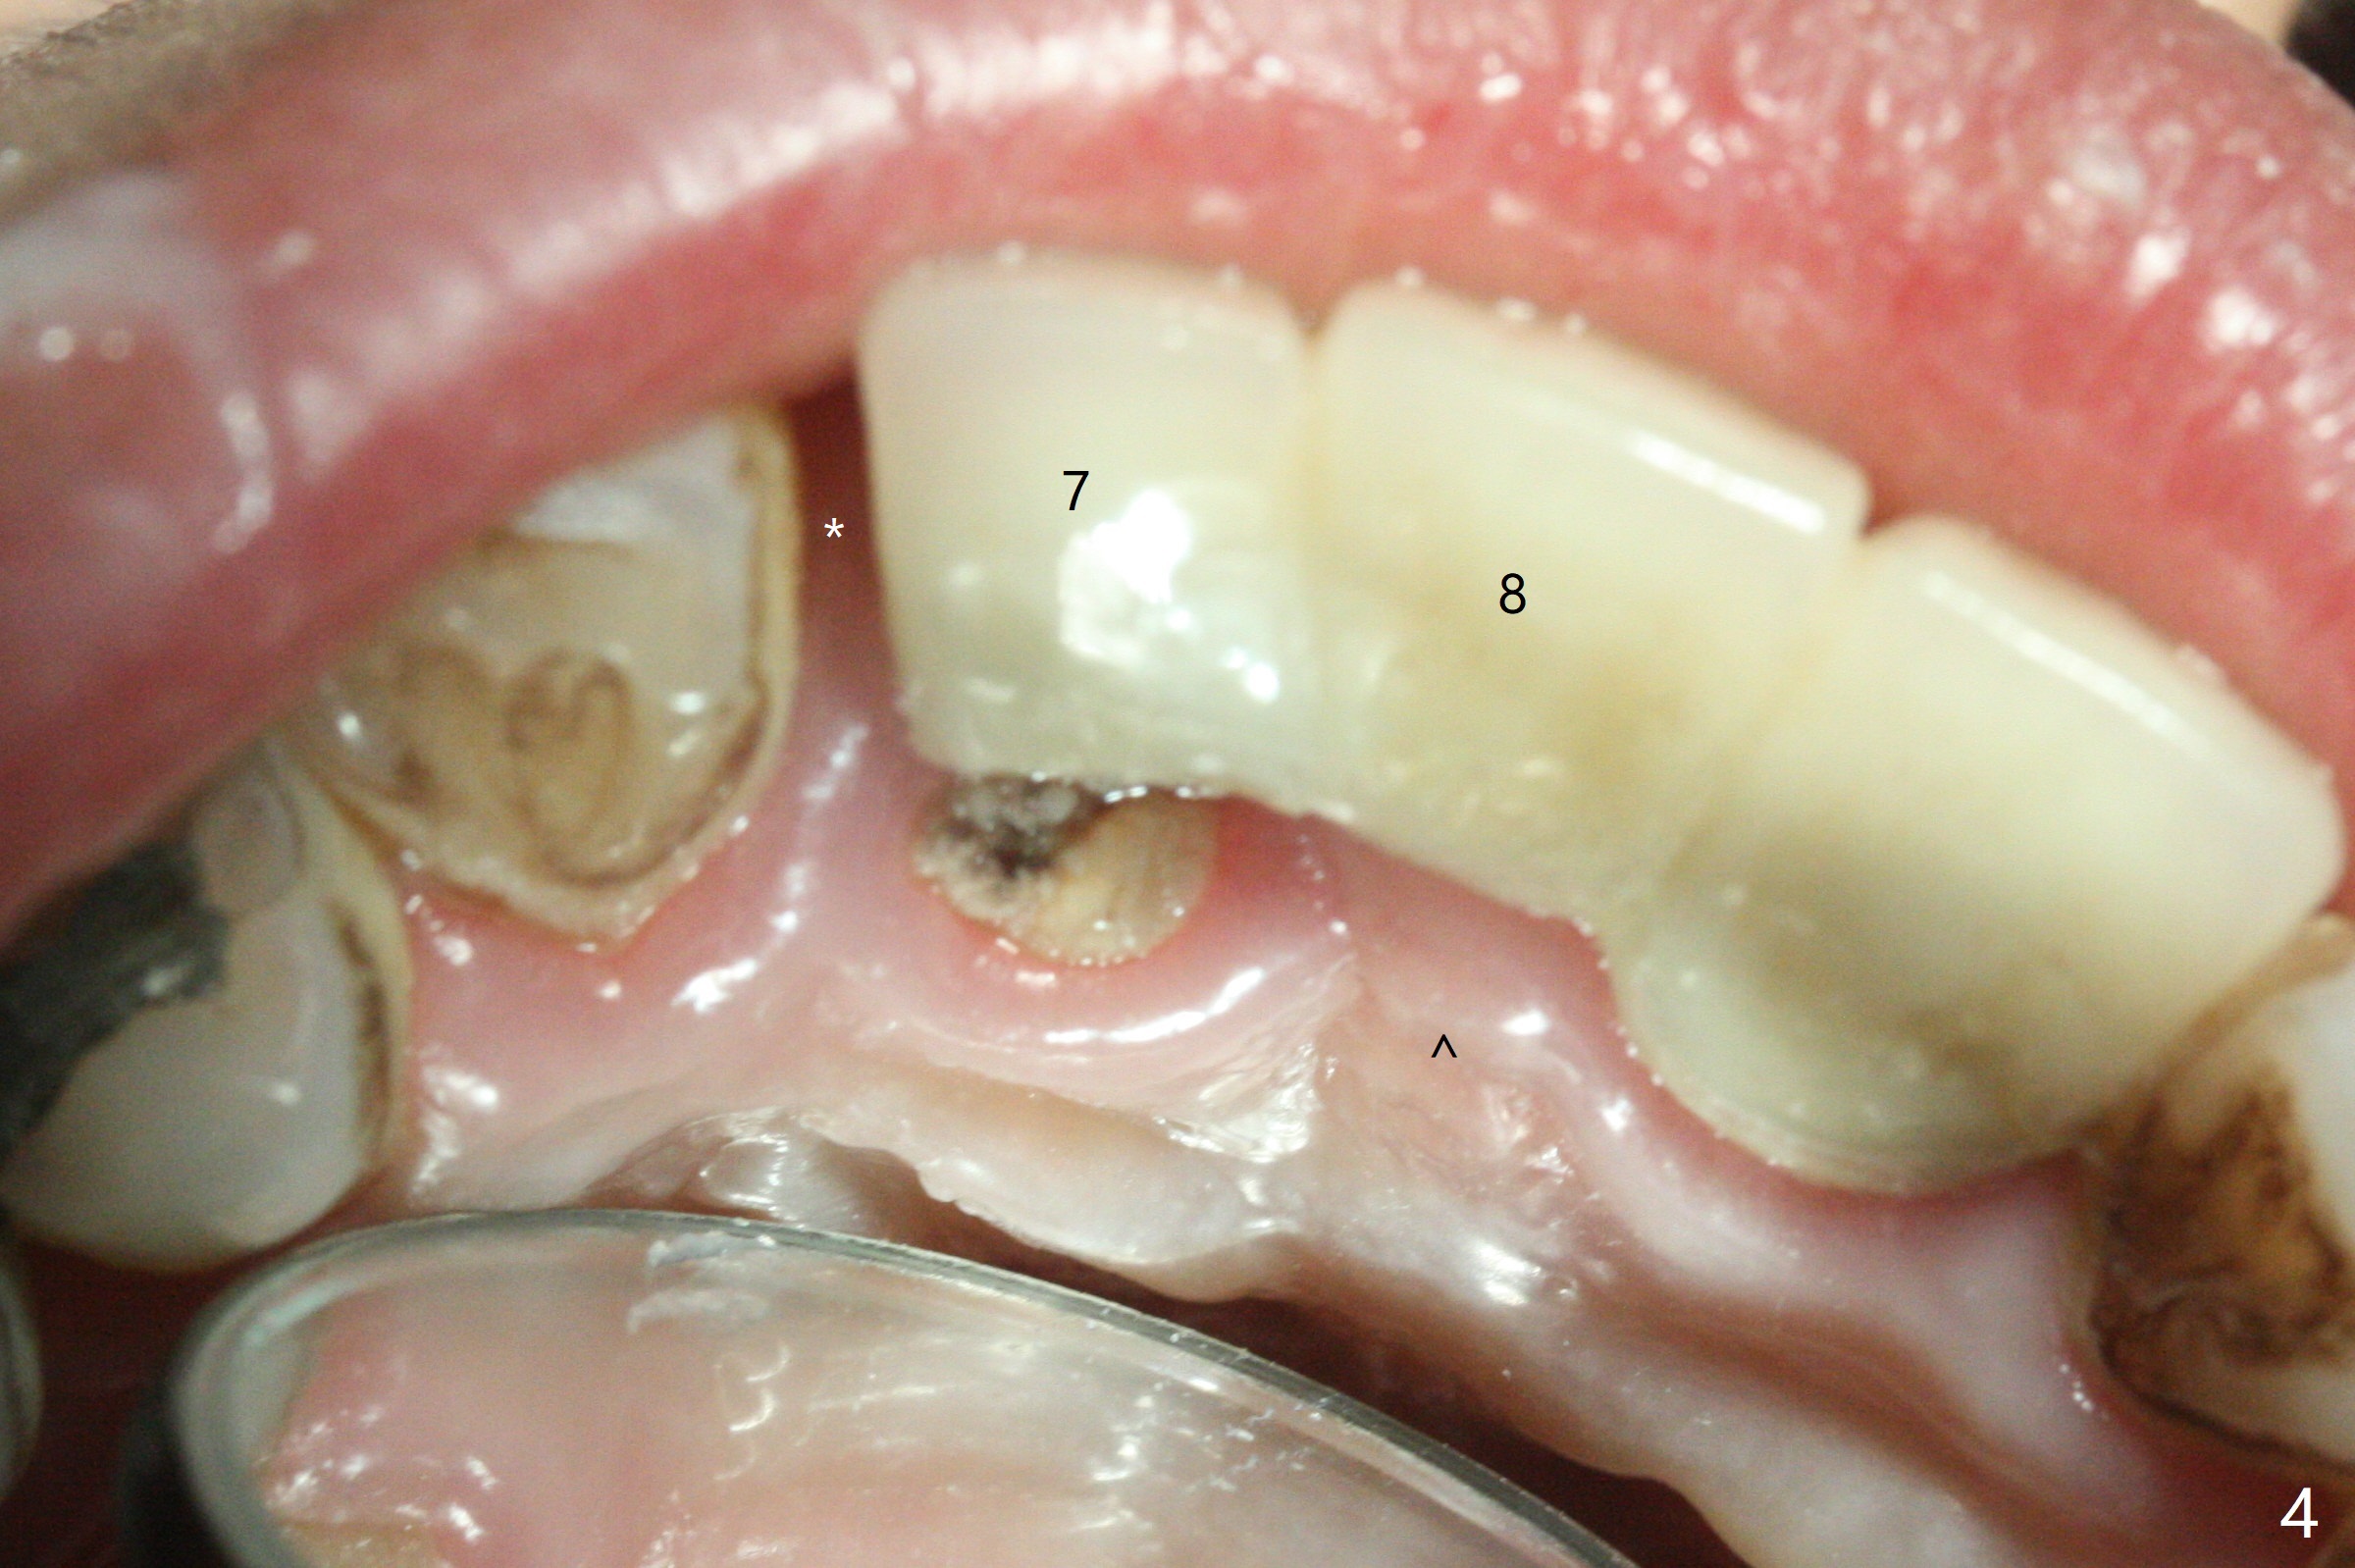

A 34-year-old woman requests fixing the failed anterior FPD (Fig.1). The edentulous alveolus looks thin; 1-piece implant may be indicated at most. A regular narrow 2-piece implant will be placed at the lateral incisor (Fig.2). CT is necessary for treatment planning. Impression has been taken for stent fabrication. 34岁女,一年半前来诊所(图一,二(侧切牙种植,做悬臂桥,暂时保留左上1牙冠)),希望修复右上门牙桥。现在终于要求立即做,基牙处牙龈红肿 (图三(今天做深洗)),牙桥颊侧移位(图四),侧切牙(7号牙)牙槽嵴也不是很宽,植入3.5毫米植体(两段式, IBS)还勉强(图五)。为了简化,避免悬臂桥,我还想在中切牙(8号牙)无牙处植入一段式2.5毫米植体(图六),适当做些牙槽嵴劈开(图六右上图:红线; from IBS cassette)。这周末徒手植入,她离开时应该有固定临时修复物。

Sequence of treatment: Section FPD between 8 and 9, photo of the narrow ridge of #8, incision, suture fixation of the flaps, ridge trimming with surgical handpiece/round diamond bur, confirmed by Tatum implant positioners (3 mm), 1.2 mm drill (8 mm deep), broken drill in place for PA later, ext #7, photos of curettes and granulation tissue removal instruments, 1.6 mm drill in the middle of the palatal slope, 1st intraop PA, #8 ridge split with IBS blade osteotome or thin surgical bur, subcrestal implant placement, fabricate temp especially for #8 before bone graft and suture to make sure subgingival margin and temp creating space for bone graft to make sure buccal and palatal bone thickness.

一段式植体似乎不美观,其实它适用于近中远中空间狭窄地方,如这个病例,而两段式植体显得太粗,没有空间形成牙龈乳头,况且容易以后导致植牙周围炎。即刻临时牙冠手术第一天就起到美观作用,术后三四个月中反复调整,为永久性牙冠奠定基础。以下手术步骤就是为了这个目的。在中切牙之间切断牙桥,为右上1狭窄牙槽嵴拍摄照片(颊侧,咬合面观),切口,铬羊肠缝线牵拉,外科车针去除尖端牙槽嵴直到后者宽度达到~ 3毫米,使用1.2毫米一段式钻头,8 毫米,插入一个已经折断同样大小车针作为定位;拔除侧切牙,拍摄各式各样刮匙和肉芽组织去除器械,用1.6毫米钻头在腭侧骨板钻洞,深度9毫米,拍摄术中第一张根尖片;在中切牙处使用片状骨凿稍做骨扩张,必要时旋转式扩大器,之后完成牙槽嵴下植体放置,侧切牙牙槽窝以及中切牙术野插入无絮棉布,做必要基台制备,使用成品临时牙冠制作两个分开牙冠,确保牙龈下边缘,取出棉布,植骨,放置PRF膜,插入临时牙冠,尤其是中切牙牙冠和骨粉将改善颊侧,腭侧(与图四箭头对比)饱满度,最后缝合,调整咬合。7,8号牙骨质密度分别为700和 500单位(图七,八)。